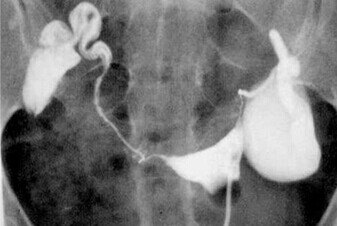

输卵管积水为慢性输卵管炎症中较为常见的类型,是指因流产、引产、不洁*交性**、盆腔感染等原因造成输卵管远端阻塞,使输卵管管壁扩张并形成积液的病理过程,是导致不孕症的重要原因。

关于输卵管积水对IVF妊娠结局的影响,研究结果显示,输卵管积水使IVF-ET 的着床率及妊娠率降低、流产率增加,主张先处理输卵管积水再进行IVF-ET,一般选择手术治疗。目前学术界对输卵管积水手术方式的选择意见不一,常用的手术方式有经阴道超声下输卵管积水抽吸术、输卵管切除术、输卵管伞端或壶腹部造口术、输卵管近端结扎术等,以及近年来开展的输卵管栓塞术等。

1、经阴道超声下输卵管积水抽吸术,其机制可能是降低了输卵管压力,防止积水流向宫腔,避免输卵管积水的液体对胚胎的毒性作用。但是此法易使输卵管积水复发,故有时需多次穿刺抽吸。

3、一些研究者主张在输卵管积水不严重的情况下应尽量保留卵巢功能,可在腹腔镜或开腹手术下行输卵管伞端或壶腹部造口术,此术式保留了输卵管,避免影响同侧卵巢血供和卵泡发育,胚胎移植的妊娠率亦可提高,缺点是有可能出现异位妊娠,个别患者输卵管积水会复发。